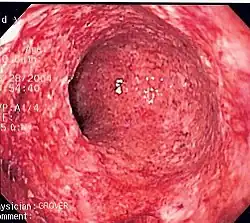

Colitis (inflammation of the colon) caused by Crohn's disease.